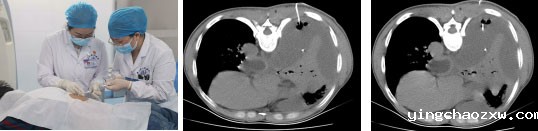

据悉,患者为男性,现年56岁,因“咳嗽、咳痰伴右侧胸痛4天”,于6月15日入住我院北院区呼吸与危重症医学科,胸部CT检查示:右侧中等量胸腔积液,叶间裂增厚积液;胸腔超声示:右侧胸腔包裹性积液;右侧胸腔内稍强回声,血供稍丰富。入院后为患者开展抗炎治疗、胸腔闭式引流术,但引流效果不佳。患者胸腔包裹性积液原因不明确,胸膜粘连,诊治比较困难。为了消除患者的痛苦,让患者早日恢复健康,科室医疗组经过审慎认真的评估,为患者制定出创伤最小、恢复最快的内科胸腔镜检查及治疗,并于6月25日为患者开展胸腔镜检查术,胸腔镜下见:右侧胸膜广泛粘连。术中为患者开展胸膜活检术,胸膜粘连松解术,既解除了胸膜粘连,又取得了活检标本。该患者最终诊断为:脓胸。术后北院区呼吸与危重症医学科继续对患者实施抗炎巩固治疗,历经21天的治疗后,患者病情恢复良好。

胸膜腔被致病菌感染,产生脓性积液集聚在胸膜腔称为脓胸,早期及时治疗可避免传统外科开胸手术治疗,而内科胸腔镜手术是治疗脓胸最为有效的方法,与传统开放性手术相比,内科胸腔镜手术具有手术切口小、术后并发症少、患者术后恢复快等优点,适应症主要有胸膜肿瘤、气胸、肺癌、胸腔积液、脓胸等。